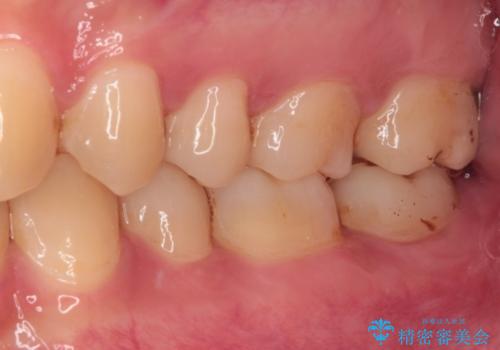

オールセラミッククラウンとしたことで見た目の改善やものが挟まる不快感の改善だけでなく、舌触りも良くなりました。